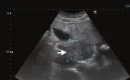

Ultrasound is a very high frequency sound wave that is passed into your body through an ultrasound probe. As it passes through the tissues, a proportion of the wave is reflected from each of the layers of tissue. The scanner picks up the returning sound waves and processes them into an image. As such, ultrasound has many applications, including being able to precisely administer a steroid injection in affected joint and area. Ultrasound-guided steroid injections have revolutionized pain management by offering a precise and effective method for delivering anti-inflammatory medication to affected areas. These injections are commonly used to treat conditions such as arthritis, tendonitis, and bursitis.

An ultrasound transducer, otherwise known as an ultrasound probe, is used to acquire the images of the affected area or areas. The probe is applied to the area that is being scanned and a water-based gel is used to allow for good contact and less friction between the prob and the skin. The probe is used to identify the where the pain is coming from and pinpoint the best place for the insertion of the needle and administration of the local anaesthetic and steroid. to be administered. As such, a thorough ultrasound investigation of the area is important before proceeding as well as discussing with the patient where they feel the most pain when doing their everyday tasks.

- Ultrasound Imaging: A gel is applied, and an ultrasound probe is used to locate the target area.